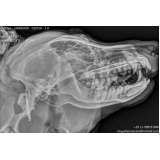

O veterinário oncologista é aquele que examina e oferece soluções aos animais de estimação que estão passando por diferentes tipos de câncer. Consultar este profissional é muito importante pois ele é capaz de diagnosticar a doença com antecedência para maiores chances de cura.

- Ultrassom com hora marcada;